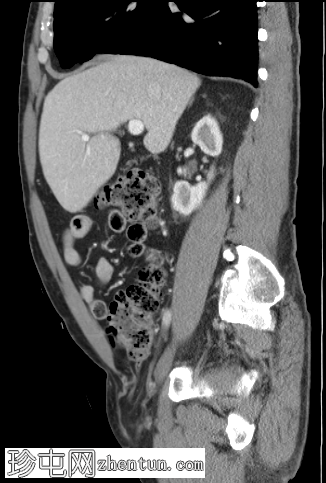

矢状C+门静脉期

右侧腹股沟斜疝,包含网膜脂肪,延伸至阴囊颈。疝囊内包含正常阑尾(轴向、冠状),符合Amyand疝。

双侧精索脂肪增多症。